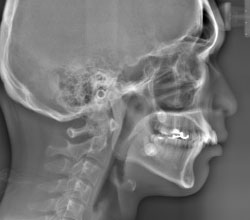

セファロ(側面)

低被ばくで、広い範囲の撮影が可能なCT(3D撮影)機器です。デジタル方式ですので、被ばく量が従来のものと比べ各段に軽減されています。

3D撮影ができることにより、多角的な診断が可能となり、インプラント治療などにおける診断をはじめ、複雑な治療である親知らずの抜歯や根管治療を安全に、且つより正確に行うことが可能です。